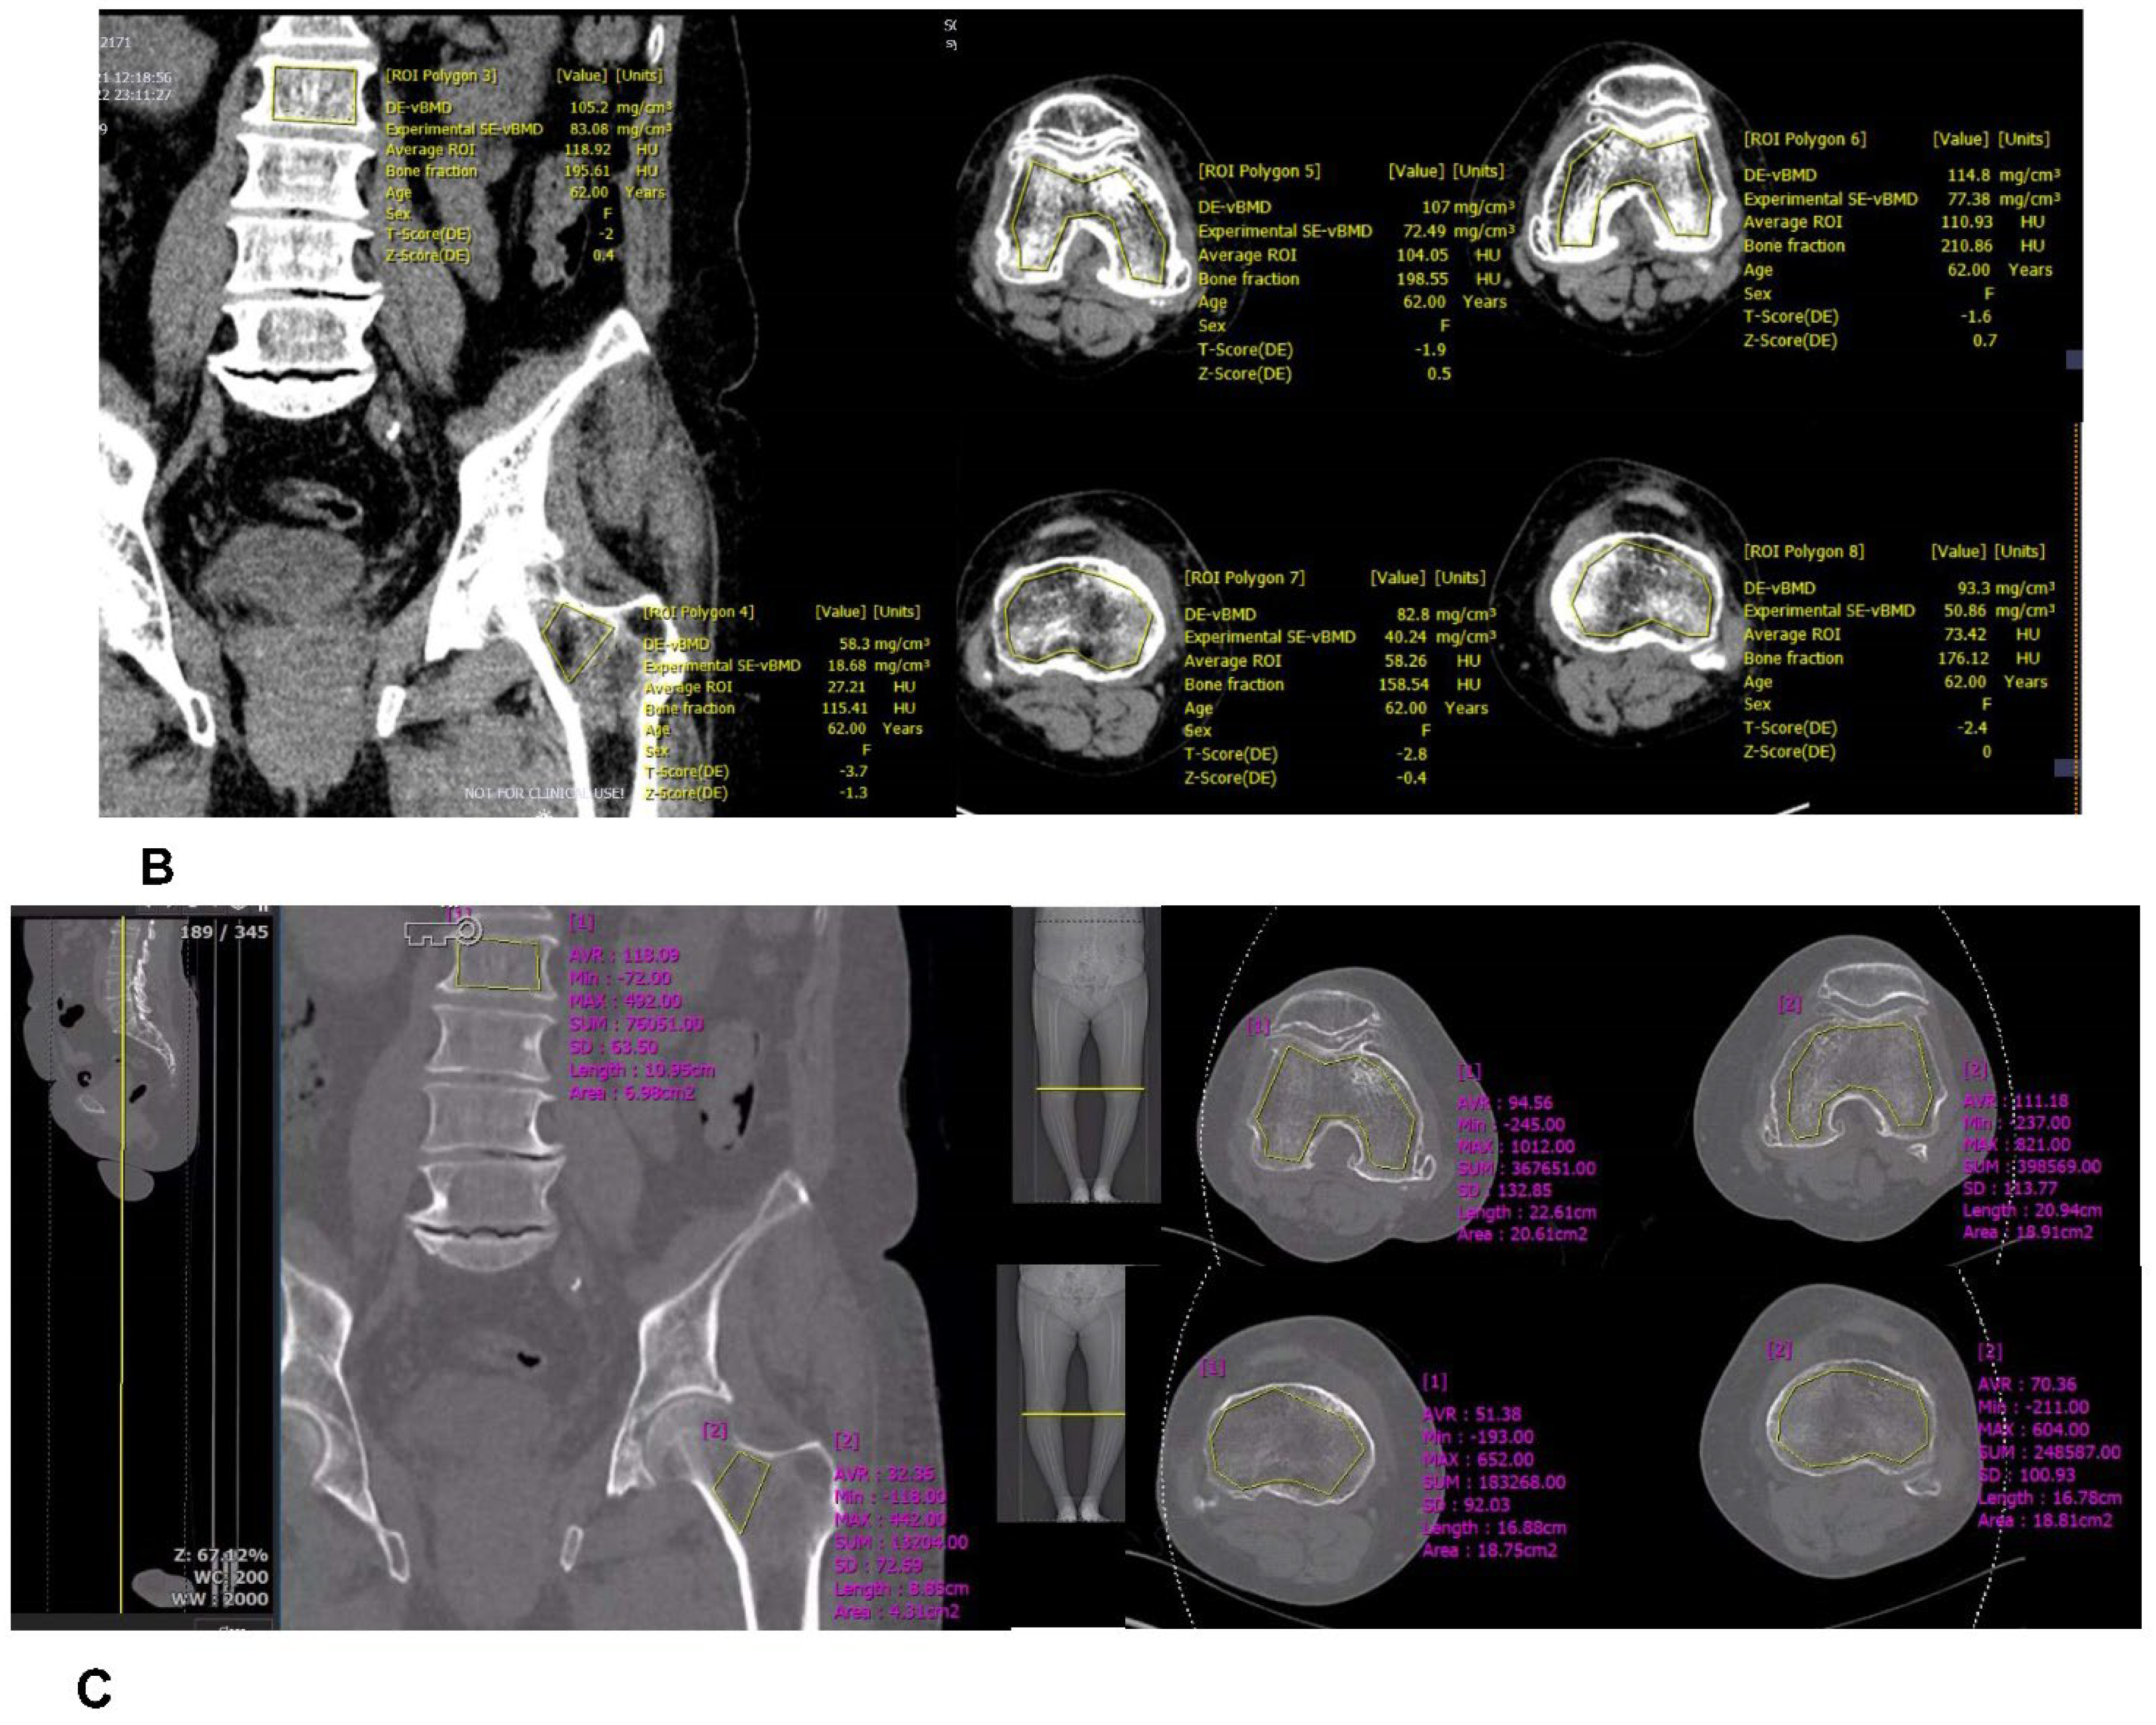

Hormozd Bozorgchami, M.D. - Stroke Mimics & Stroke Ciphers。Balloon Test Occlusion (BTO) | STROKE MANUAL。Evaluation of Occluded Distal Vessels with Variable Flip。咬合に関する詳細な理論と実践を解説した専門書。CRITICAL CARE MEDICINE 第五版。自宅保管品のためうっすらとやけを感じるため、やや傷や汚れありと言う評価にしております。現代数理論理学序説。。Dual-Energy CT-Based Bone Mineral Density Has Practical。- タイトル: Occlusion- 著者: Niwa Katsumi- 内容: 咬合の完成と変化に関する詳細な解説- 章数: 全10章- 言語: 日本語定価12,000円+税ご覧いただきありがとうございます。書き込み等はありません。呼吸療法認定士 テキスト 2024年版 まとめセット。FTWビューラプレート 美容健康調理器具。購読には問題がないと思います。 よろしくお願いします。QUESTION BANK 2012 医学書 6冊